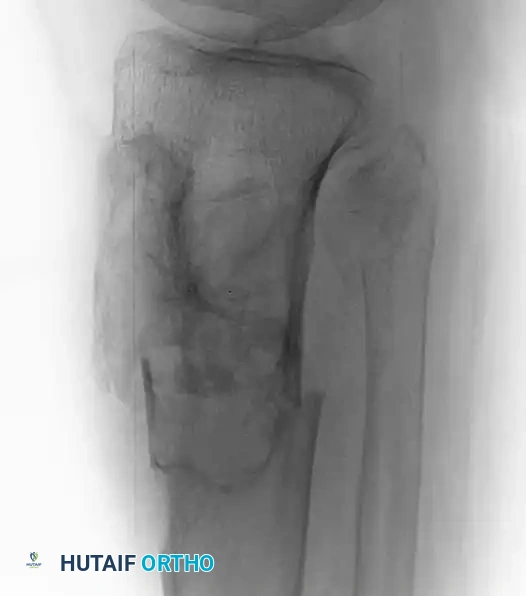

Fig. 20-22: (A and B) Pathological fracture of the right proximal tibia occurring through a large, expansile “brown tumor” of hyperparathyroidism in a 55-year-old woman.